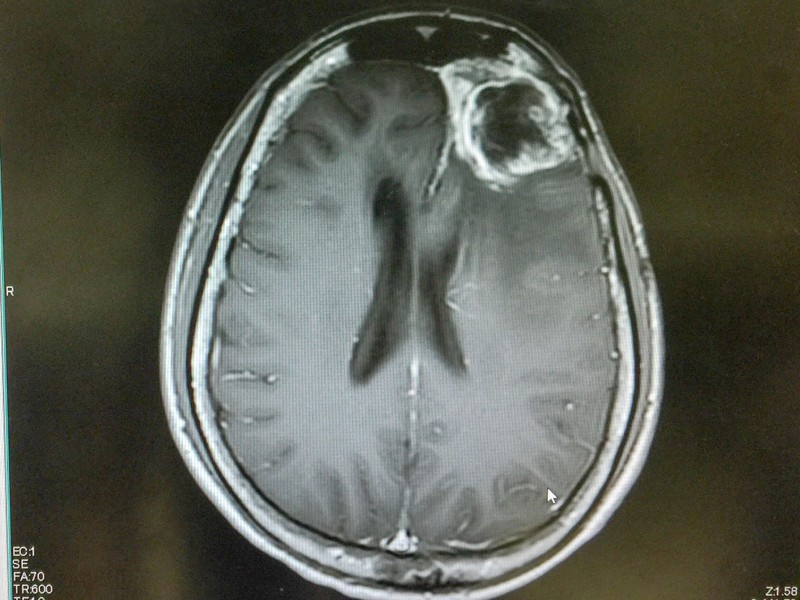

Glioblasztóma

Az édesanyánál glioblasztómát, a legagresszívebb agydaganatot diagnosztizálták.